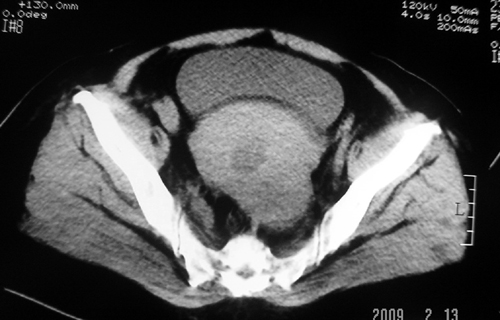

以下是引用余辉在2009-2-14 8:37:00的发言:[br]宫颈左后壁见较大低密度肿物影且向左后上方突出,宫腔内见大片状低密度区,考虑宫颈肿瘤,宫颈癌可能性大,伴宫腔积液或转移